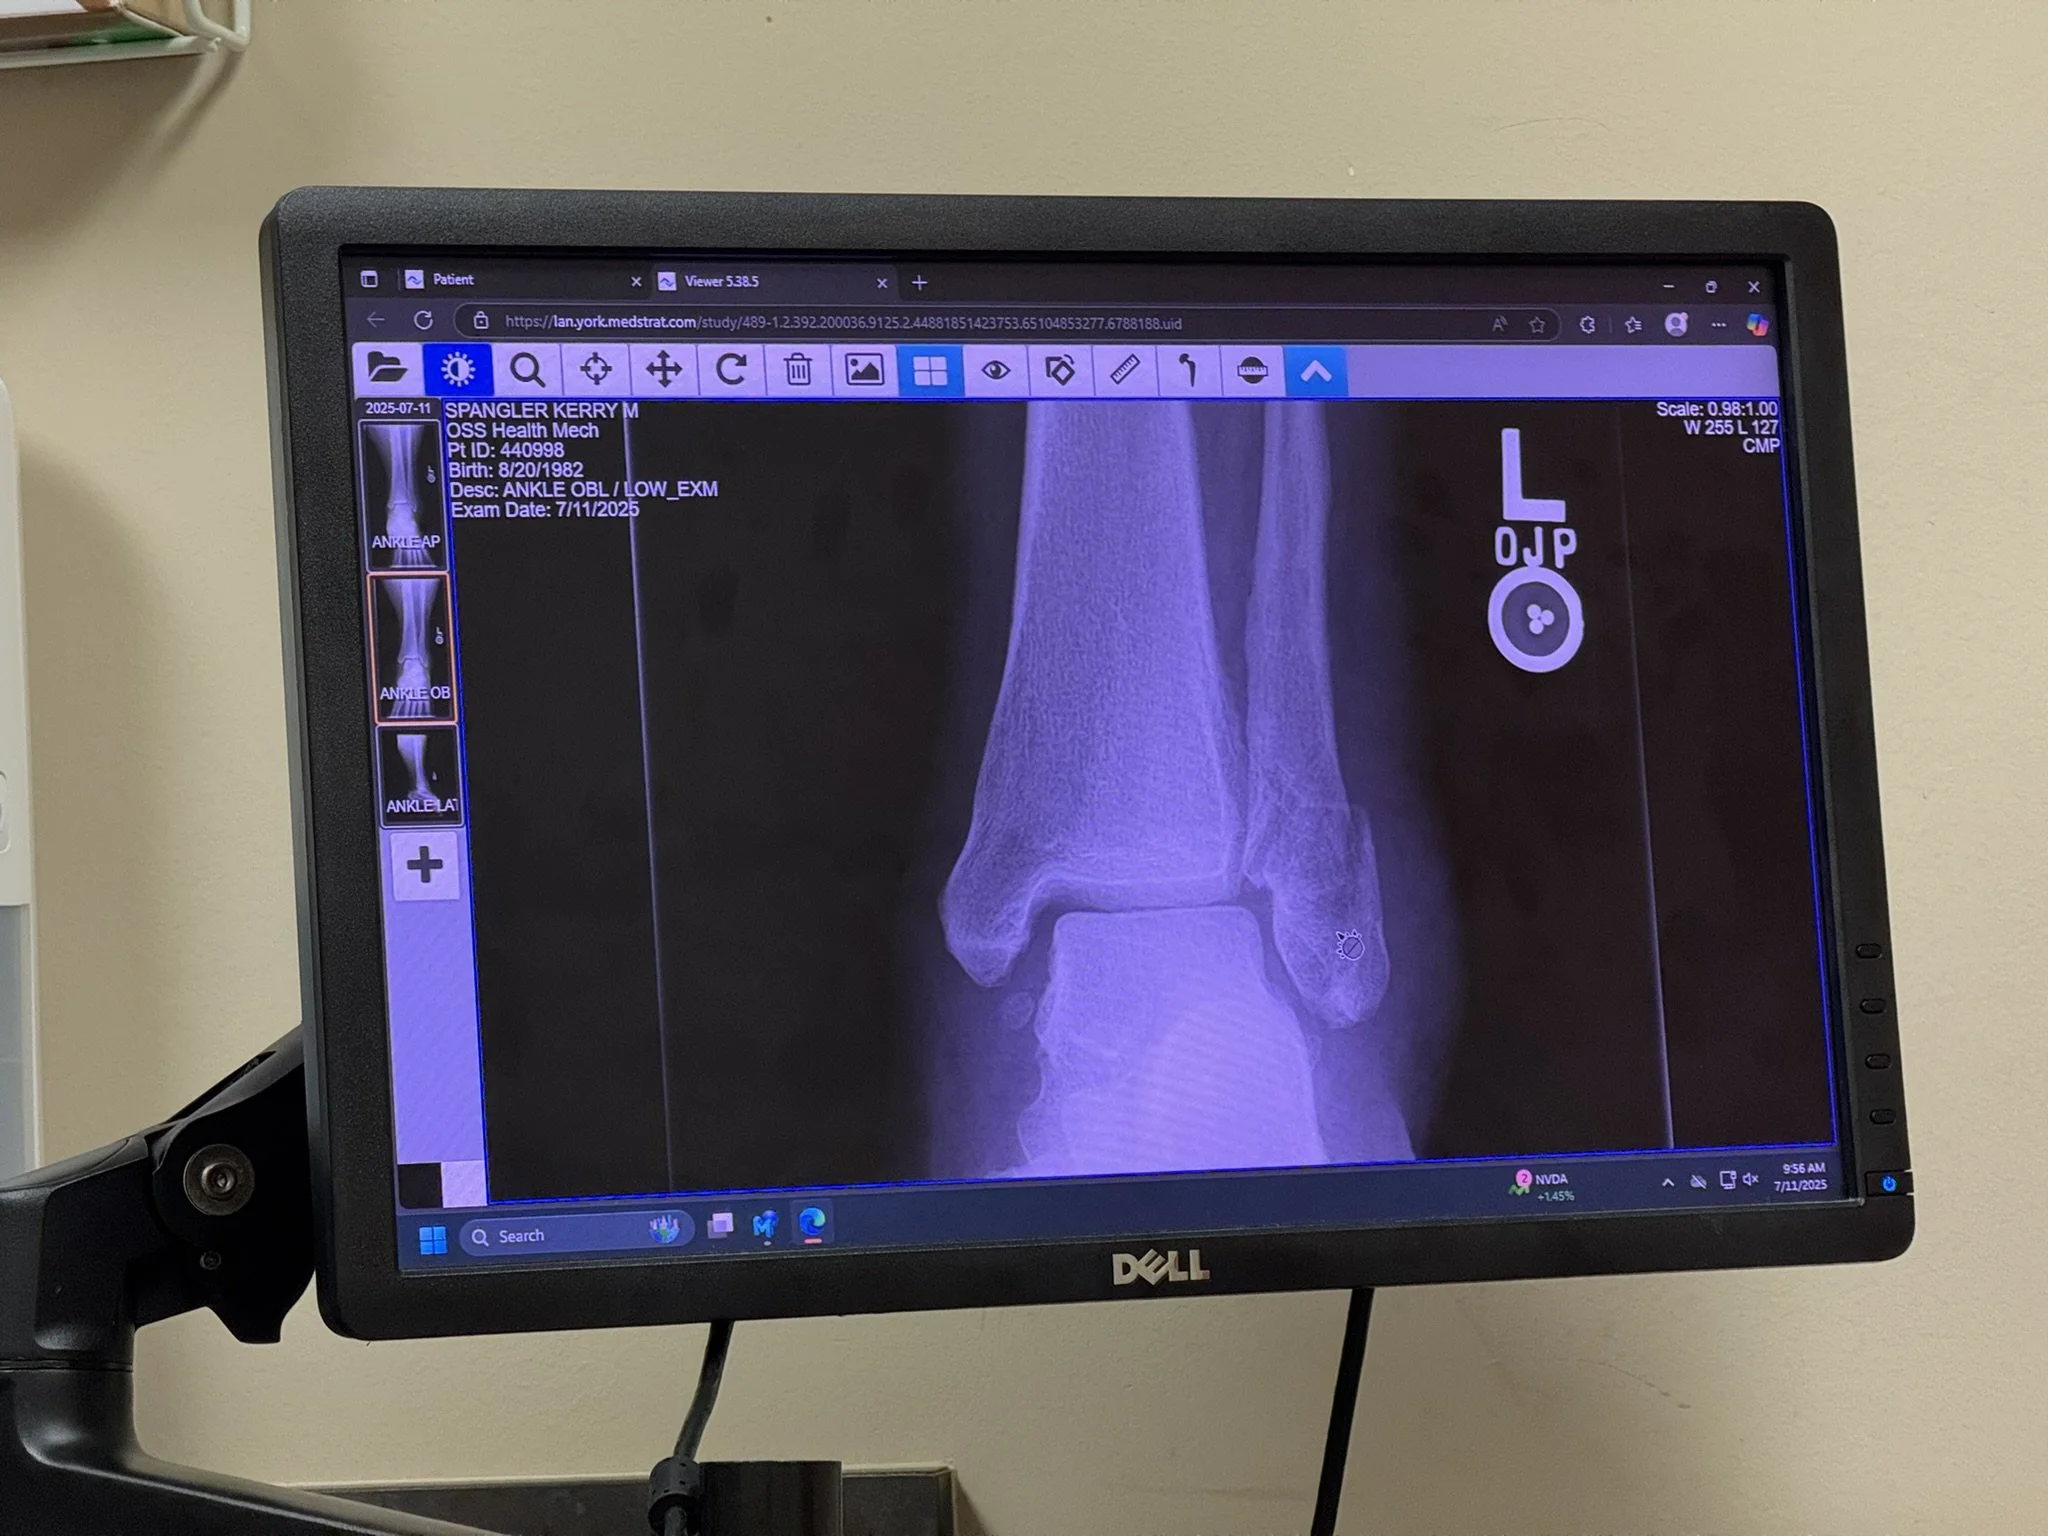

Spent most of the weekend at the hospital, not for myself, but what a weekend. Friday morning, got to work, phone rings. It’s my wife! She has fallen down the stairs and broken her ankle.

Packed up, drove back home, and long story short spent about three days at Hershey Medical. Wife is back home now, however immobile, and living that living room life.